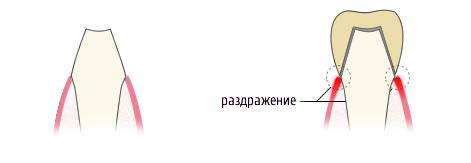

Металокераміка з плечової масою

Плечова маса на металокераміці робиться для підвищення естетичних якостей протеза і виготовляється з зовнішньої (видимої) сторони, для уникнення просвічування металу через ясна. Зуб під металокерамічну коронку з плечової масою обточується з уступом. Уступ вимагає від лікаря спеціальних навичок і призначається для запобігання подразнення контактної зони кераміка-метал-ясна. Якщо ви уважно подивитеся на малюнок, то інтуїтивно зрозуміло, що обточування зуба з уступом краща. Вартість і роботи і самої металокерамічної коронки в цьому випадку вище.